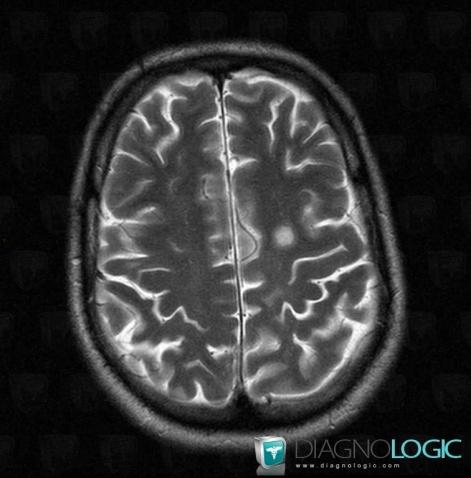

Multiple sclerosis, Cerebral hemispheres, MRI

Here is the specific information in the key image above:

- Diagnosis Multiple sclerosis, Location(s) Cerebral hemispheres, with gamuts White matter disease, Multifocal intracranial lesions, Intracerebral T2W or FLAIR hyperintense lesion